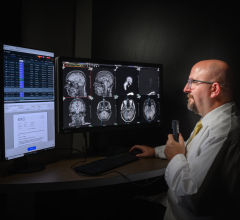

November 2, 2012 — ClearCanvas Inc. announced the commercial release of ClearCanvas radiology information systems/picture archive and communications systems (RIS/PACS) Team Edition, an end-to-end radiology workflow management solution.

The system is U.S Food and Drug Administration (FDA) cleared and CE marked and provides fully integrated radiology workflow and data management solution.

The RIS/PACS is built on the popular ClearCanvas software platform, currently in use by over 25,000 users and partners. The easy to use workflow solution has been designed to enable a practice to efficiently serve patients from the time they walk in the door to the time they receive their results.

The Team Edition includes key features such as drag and drop scheduling, customizable work lists, roaming user profiles, hanging protocols and digital report dictation. With web-based image viewing and the Referring Physician's Portal, it has also been designed for efficient and easy access to both patient images and associated reports.